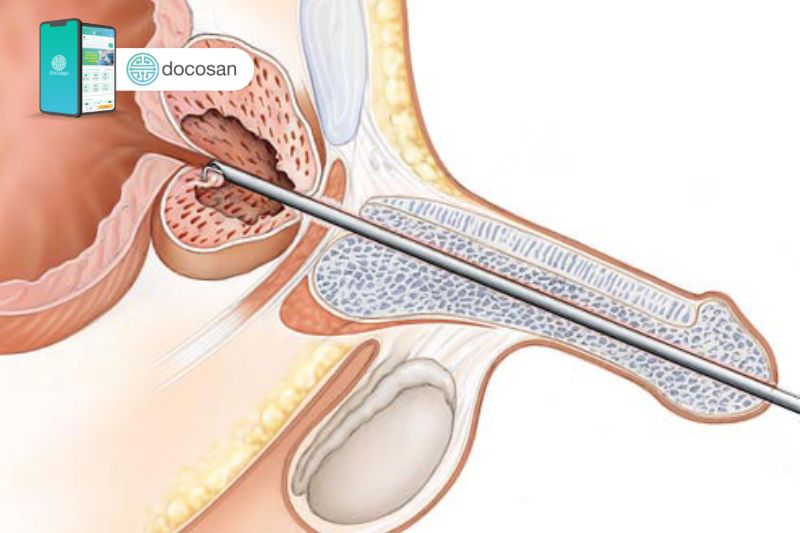

Hiện nay không phải bệnh nhân có kích thước phì đại tiền liệt tuyến nào cũng cần mổ. Những đàn ông bị ảnh hưởng đến sức khỏe nhiều do triệu chứng bệnh và phì đại tuyến tiền liệt điều trị nội khoa không đạt hiệu quả thì cần được chỉ định điều trị ngoại khoa. Bệnh nhân được chỉ định mổ điều trị kích thước phì đại tiền liệt tuyến khi tuyến tiền liệt to trên 60 gam và kèm theo một số bệnh lý do tắc nghẽn đường tiết niệu.

Phương pháp mổ nội soi

Hiện nay, phổ biến và an toàn hiệu quả nhất là áp dụng phương pháp cắt bỏ tuyến tiền liệt bằng nội soi qua đường niệu đạo. Bác sĩ sẽ đưa dụng cụ nội soi rất nhỏ vào tuyến tiền liệt qua đường niệu đạo bệnh nhân để tiến hành phẫu thuật cắt bỏ các khối u xơ và hút bỏ ra ngoài cơ thể qua đường tiểu.

Toàn bộ quá trình phẫu thuật này được kiểm soát qua màn hình máy tính hiện đại và thời gian thực hiện kéo dài khoảng 60-90 phút. Phương pháp này khá nhanh mà không gây đau đớn nhưng hiệu quả kém vì có thể tái phát trở lại do không loại bỏ hết u tuyến tiền liệt.